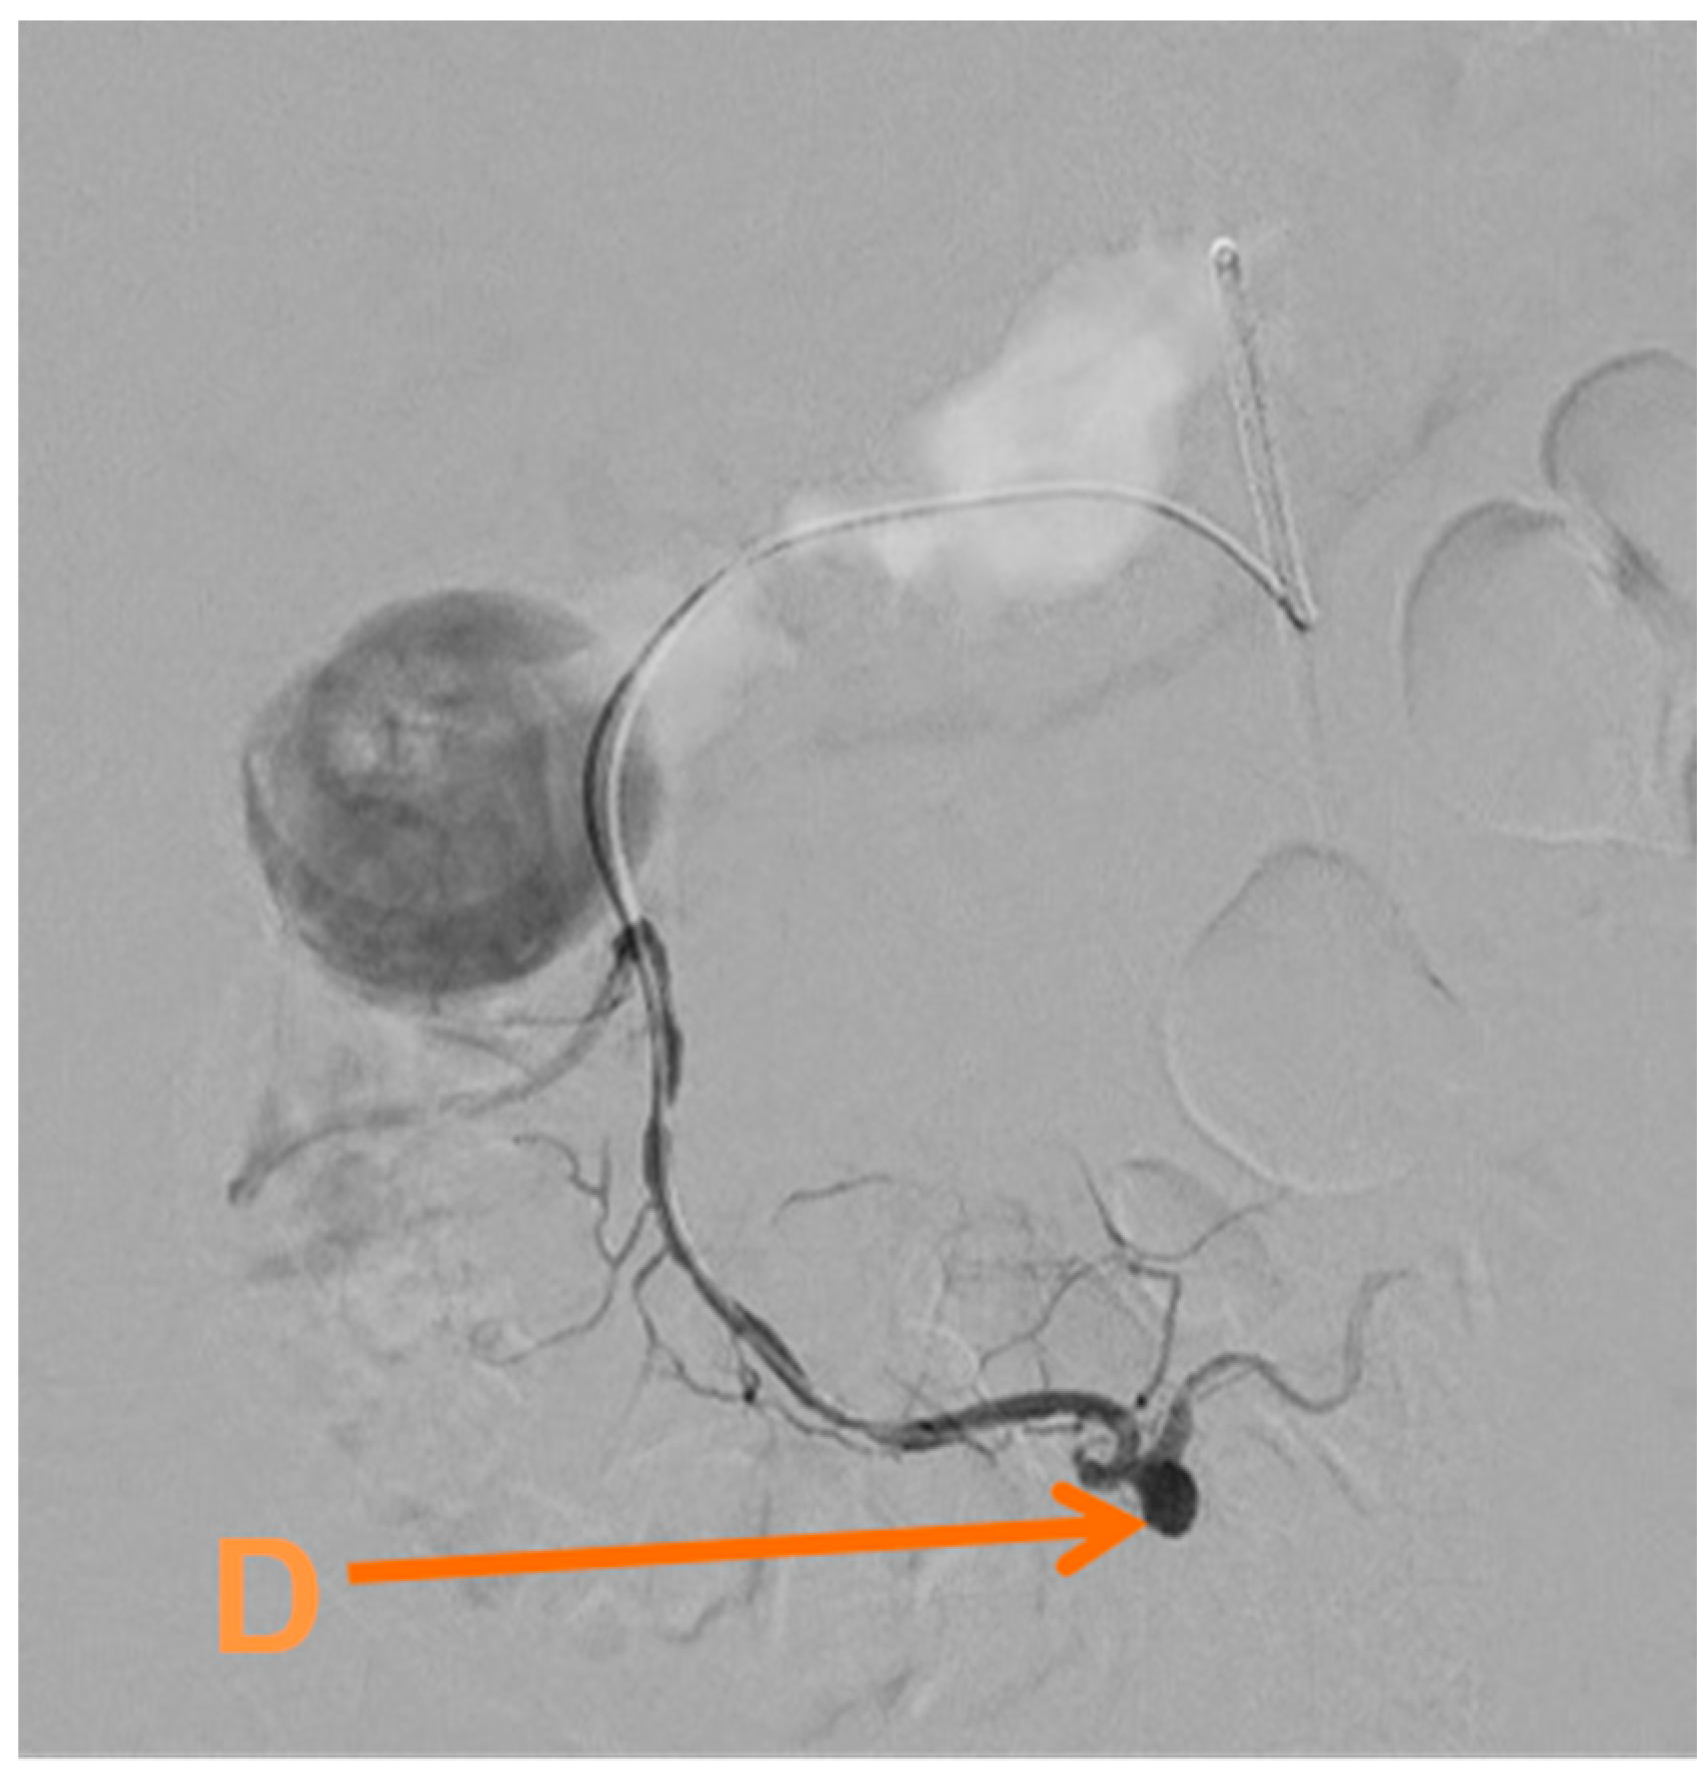

Given her condition and the pathology found, she underwent an embolisation of the inferior pancreaticoduodenal artery via the common femoral artery (Figure 3) on day twenty-six. This was performed using a SIM1 catheter to catheterise the coeliac axis and gastroduodenal artery, revealing reverse flow in the gastroduodenal artery.

Figure 3.

Selective angiogram showing (D) a pseudoaneurysm of the inferior pancreaticoduodenal artery.